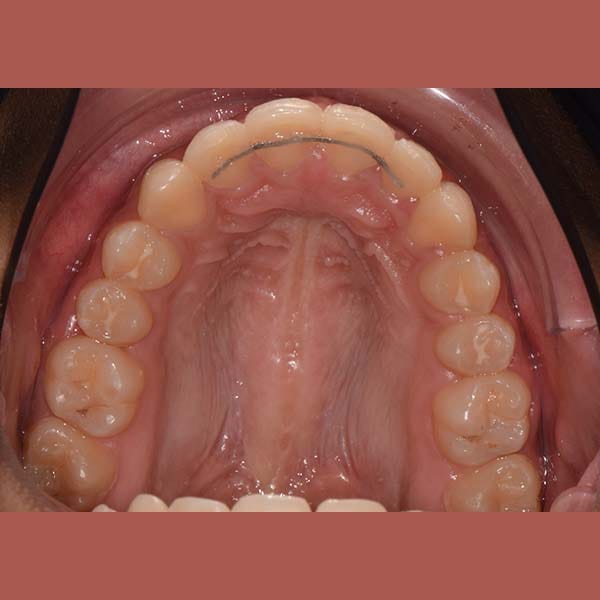

بعد

ابتسامة جميلة جدا